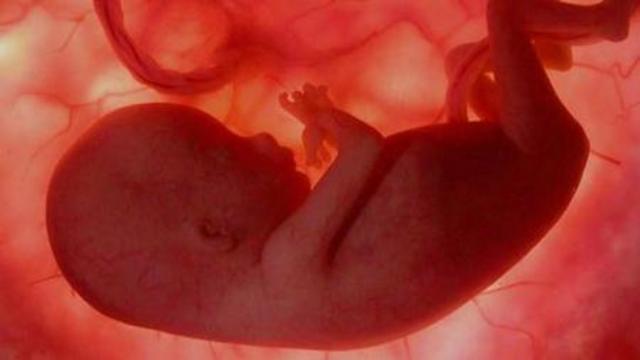

Todos los sistemas principales del cuerpo y órganos como el estómago, el hígado, los pulmones, el páncreas y los intestinos están formados y en su sitio, aunque no están desarrollados del todo. La cabeza llega a ser más redondeada y su perfil se va definiendo.

Además, empezarás a escuchar el latido del corazón del bebé con más facilidad.

Todavía mide 6 centímetros y tiene unos 14 gramos de peso.